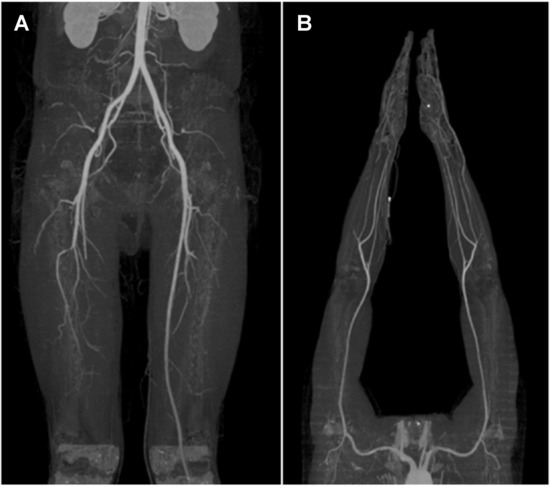

After consultation with a vascular surgeon, the patient was advised to take cilostazol along with medications for Buerger’s disease, including alprostadil (Eglandin), beraprost, and nafronyl oxalate. Medication, smoking cessation, necrotic tissue debridement, wound repair, and persistent aseptic dressing with local oxygenation therapy (Figure 1B) were performed; the necrotic tissue biopsy results were of simple ‘necrosis’. The skin epithelialized well without complications, and the stitch was removed 14 days after wound repair. In subsequent outpatient observations, the wound fully recovered and was maintained (Figure 3). The patient provided informed consent for the publication of this case and related imaging findings. Written informed consent was obtained for publication of this case report and accompanying images.

Figure 3.

Four-month follow-up images showing satisfactory recovery without serious complications.